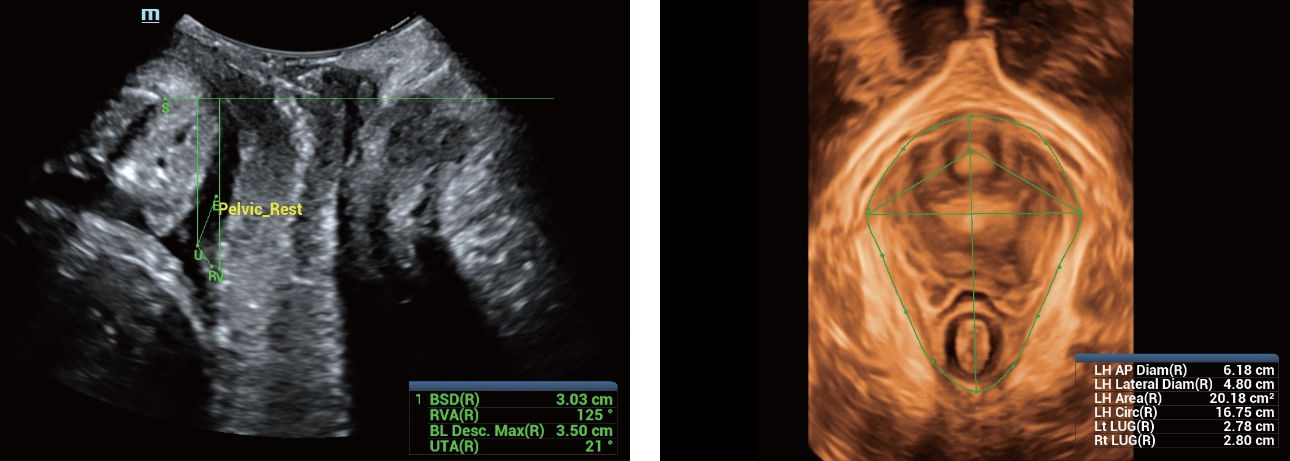

Neben der erstklassigen Bildqualit?t verbessert Resona 7 auch die klinischen Forschungsm?glichkeiten mit dem revolution?ren V Flow f├╝r die vaskul?re h?modynamische Bewertung und der intelligentesten Ebenenerfassung aus 3D-Datens?tzen f├╝r die f?tale ZNS-Diagnose. Mit der Kombination aus intuitiver, gestenbasierter Multi-Touch-Bedienung und allen wichtigen klinischen Funktionen ist das Resona 7 ein echter Wegbereiter f├╝r neue Ultraschall-Innovationen.